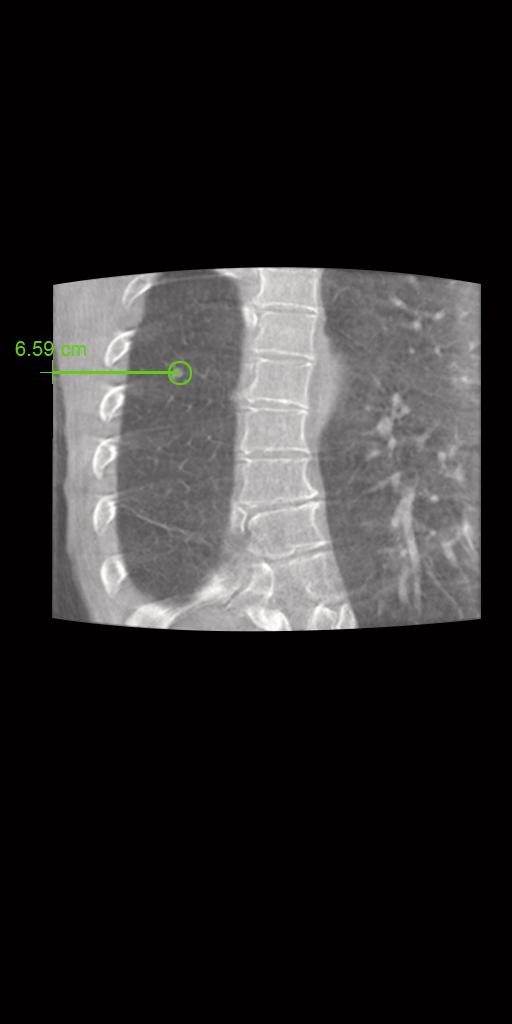

syngo DynaCT

myNeedle Companion harmonise la planification et le guidage des procédures percutanées avec aiguille pour plusieurs modalités. Le flux de travail et l’interface utilisateur sont ainsi unifiés sur les systèmes d’angiographie et TDM. myNeedle Companion permet de réaliser des procédures de routine ou avancées.

Le flux de travail débute avec syngo DynaCT,

qui vous permet de visualiser les lésions et l’anatomie.

myNeedle Guide

Avec myNeedle Guide, vous pouvez planifier un ou plusieurs trajets d’aiguille et cibles différentes. Vous pouvez également fusionner des ensembles de données provenant de plusieurs modalités.

syngo Dyna3D

Confirmez le placement

de l’aiguille et de

la zone d’ablation avec syngo Dyna3D.

En imagerie pulmonaire, syngo Dyna3D

offre une excellente qualité d'image avec une dose réduite.1